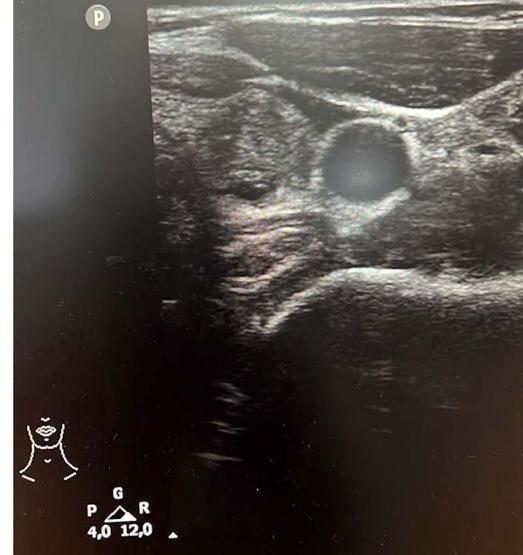

Endokrinoloji ve Metabolizma Hastalıkları Uzmanı Dr. Ahmet Suat Demir, tiroit nodüllerinin oluşumundaki en yaygın nedenin iyot eksikliği olduğunu belirterek, "Tiroit nodülleri; iyot eksikliğinin olduğu endemik bölgelerde, toplumun yaklaşık yüzde 15’inde görülebilmektedir. Kadınlarda yaygın olmakla birlikte, çevresel ve genetik faktörler tiroit nodül riskini de artırmaktadır" dedi.

Tiroit nodülü vakalarında son yıllarda artış yaşandığı gözlenirken, uzmanlar, bu artışın en yaygın sebebinin iyot eksikliği olduğuna dikkat çekiyor. Ses kısıklığı, yutma güçlüğü ve nefes darlığı gibi belirtilerle ortaya çıkabilen nodüller, artan farkındalık ve ultrason sayesinde semptomsuz hastalarda da saptanabiliyor. Nodüllerin yüzde 10 ila 20’sinin kötü huylu olabileceğini, düzenli takip ve erken teşhisin büyük önem taşıdığı belirten uzmanlar, sigara kullanımı ve genetik yatkınlığın risk faktörleri arasında yer aldığını belirtirken, özellikle kadınlarda tiroit kanseri görülme oranının daha yüksek olduğunu vurguluyor.

Endokrinoloji ve Metabolizma Hastalıkları Uzmanı Dr. Ahmet Suat Demir, tiroit nodülü vakalarının besinlerdeki iyot eksikliğinden kaynaklandığını belirterek, “Tiroit nodüllerinin oluşumunda en sık karşılaştığımız neden iyot eksikliğinin olmasıdır. Tiroit nodülleri; iyot eksikliğinin olduğu endemik bölgelerde, toplumun yaklaşık yüzde 15’inde görülebilmektedir. Kadınlarda yaygın olmakla birlikte, çevresel ve genetik faktörler tiroit nodül riskini de artırmaktadır. Tiroit nodülleri büyüdüğünde 'bası bulgusu' ile kendini belli eder. Belirtileri ise ses kısıklığı, yutma güçlüğü, nefes darlığıdır. Boğazınıza dokunduğunuzda elinizde nodülü hissetmeniz ile de varlığını anlaşılabilir. Tiroit nodülü oluşumunda, Doğu Karadeniz Bölgesi'nde lahana tüketimi suçlanmaktadır. Fakat bunun sebebi besinlerdeki iyot eksikliğidir" dedi.

Tiroit nodülü tespitinde farkındalığın artığını ifade eden Dr. Demir, "Nodül tespitindeki farkındalığımız arttı. Tiroit ultrasonu kullanıyor olmamız da bu artışa etken oldu. 'Bası bulgusu' ile dokunarak muayene ettiğimizde; mevcut olan nodüllerin yaklaşık yüzde 20’sini tespit edebiliyoruz. Nodüllerin birçoğunun özelliklerini ve boyutlarını ise tiroit ultrasonu ile tespit ediyoruz. Son dönemlerde vakalarda artış var. Bazen hiçbir semptomu olmayan hastalarda da tiroit nodülleri tespit ediyoruz. Nodülleri özelliklerine göre değerlendirerek gerekli hastalardan biyopsi alıyoruz. İyi ya kötü huylu nodüle göre tedavi uyguluyoruz. Nodülü belli aralıklarla takip ediyoruz. Tiroit nodüllerinin yüzde 10 ila 20 kadarı kötü huylu olabiliyor. Birçok kanser türü erkek hastalarda fazla görülürken, özellikle tiroit kanseri sıklığı kadın hastalarımızda daha yüksektir. Kadın hastalar daha sık muayeneye geliyor ve farkındalıkları daha yüksek" diye konuştu.